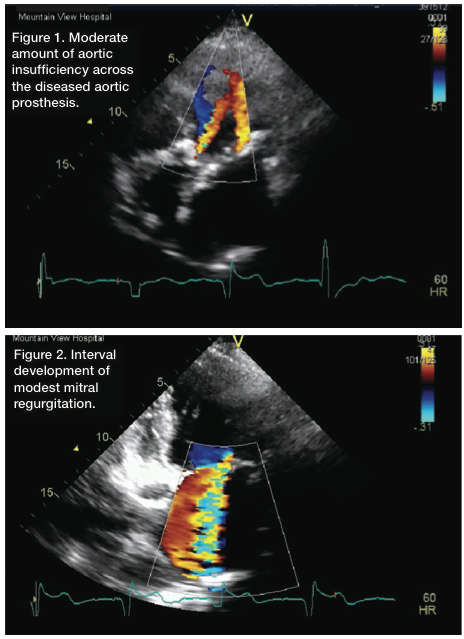

Recently, she was admitted to our local hospital with a syncopal event. Her functional status also had declined to a New York Heart Association functional class III status at baseline. Her echocardiogram revealed deterioration in LV function, with an ejection fraction of about 35-40%, and she also was found to have a modest amount of mitral regurgitation in addition to her severely diseased aortic valve bioprosthesis (Figures 1-2). Coronary angiography was performed, and her bypasses were seen to be patent, with no evidence of progressive disease elsewhere.